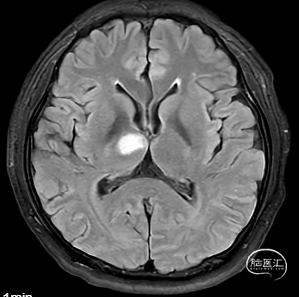

右侧中脑-丘脑可见新发脑梗塞:

CT(CTA)检查提示:右颈内动脉C7段大小约3.6×3.8×3.6mm及基底动脉远端动脉瘤形成大小约9.7×7.6×9.3mm。

1.颅内多发动脉瘤

右侧P1-P2段夹层动脉瘤

右侧A1段动脉瘤

2.脑梗塞